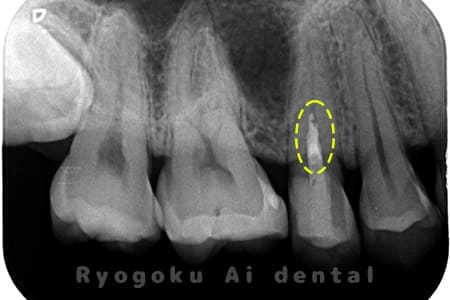

Case02

- 原因

- C3、インレー不適合

- 治療期間

- 1ヶ月

- 治療内容

- 断髄治療

- 治療費用

- 66,000円

虫歯の治療と銀歯のやり直しを希望され、銀歯を外したところ、虫歯が大きく、神経の処置が必要と判断。患者様と相談し、神経を残す断髄治療となったケース。

<リスク・副作用>

術後は痛み、腫れ、痺れなどの副作用が生じる場合があります。症状が再発する可能性があります。その場合は抜髄する必要があります。